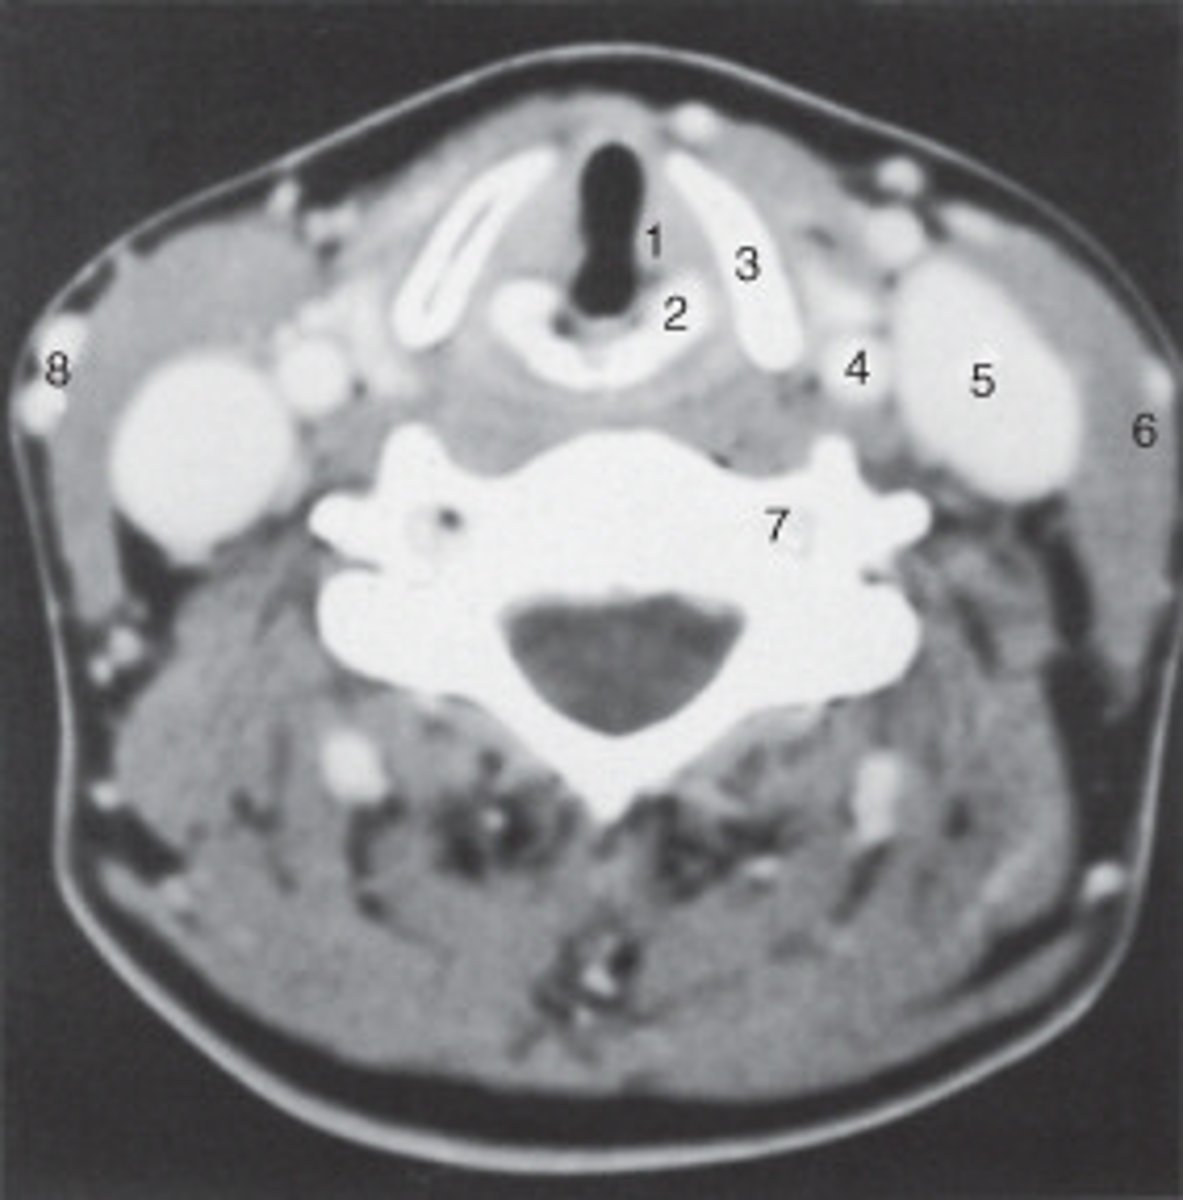

The structure labeled as 1 is the:

<p>The structure labeled as 1 is the:</p>

The thyroid cartilage is labeled:

<p>The thyroid cartilage is labeled:</p>

The common carotid artery is labeled:

<p>The common carotid artery is labeled:</p>

The structure labeled as 5 is the:

<p>The structure labeled as 5 is the:</p>

the intervertebral disk is labeled:

<p>the intervertebral disk is labeled:</p>

The structure labeled as 4 is the:

<p>The structure labeled as 4 is the:</p>